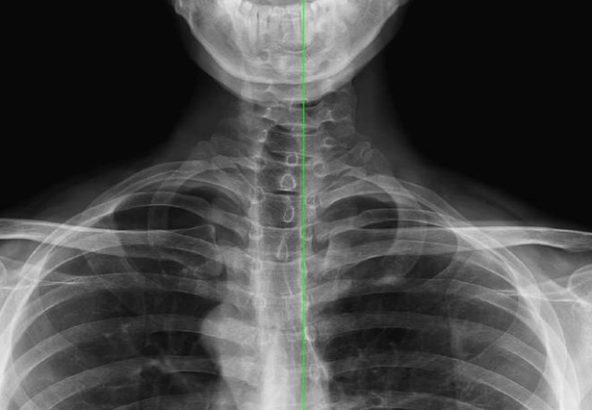

レントゲン評価【病理】

レントゲン評価